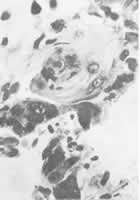

图2 原发性肝鳞状细胞癌,中央部可见角化珠 HE×600